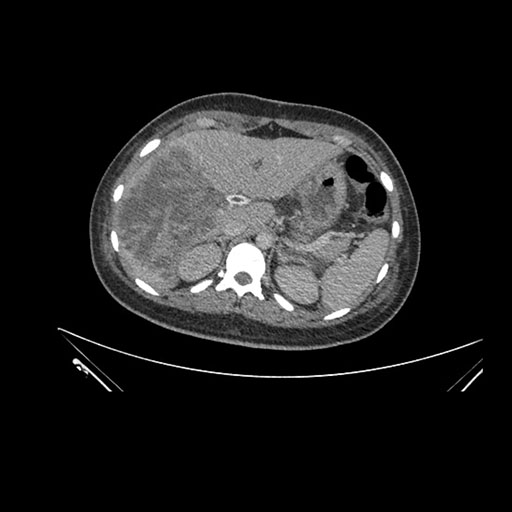

Imaging Analysis

Look through the patient's CT scan to identify any areas of concern for the necessary procedure.

Axial Venous

Based on initial findings, which issue(s) would you be most concerned about?